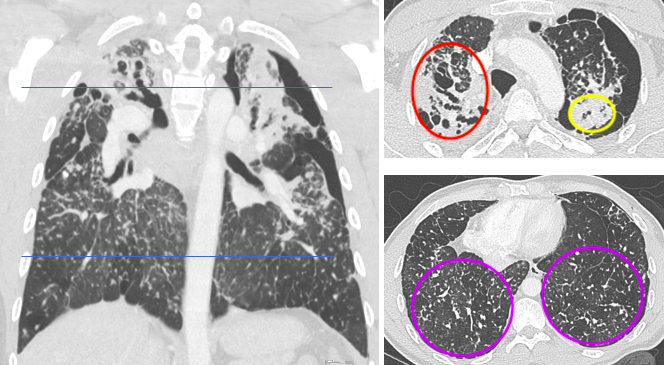

Contrast-enhanced chest computed tomography (CT) with upper predominant fibrosis/lung scarring (red oval), solid masses adjacent to a left-sided pneumothorax (yellow oval) and diffuse silicotic nodules (purple ovals). This patient had a history of working in the countertop cutting industry (15 years), smoking cigarettes (10 pack-years), and active tuberculosis (treated 7 years prior and excluded at the time of this image with laboratory testing).